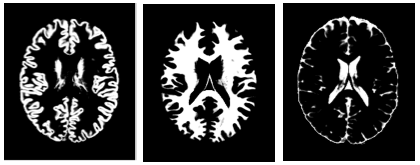

The input object is a 4D volume where the fourth dimension is a tissue-type. The object can be a segmented anatomical voxel model from any source (with ideally voxel sizes of 1x1x1mm). For example, if the object is a brain, then a segmented anatomical voxel model would be a collection of tissue templates: three-dimensional anatomical images of distinct tissue types (e.g. one template of grey matter, another of white matter and a third of cerebro-spinal fluid (CSF)). The image on the right shows cross-sections of the tissue templates derived from the anatomical images of grey matter, white matter and CSF (ordered from left to right). The voxel values in these templates reflect the proportion of tissue present in that voxel, in the range [0,1].